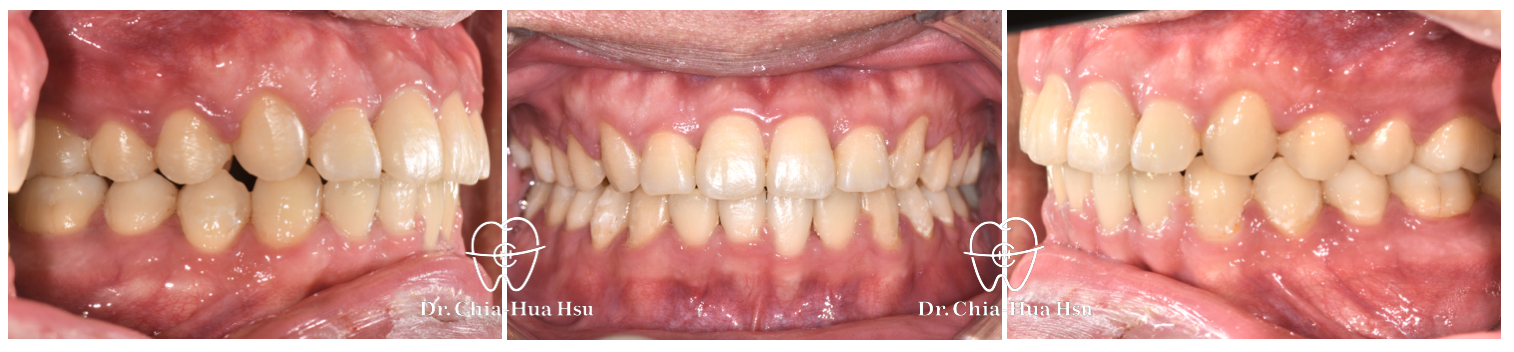

• 問題分析:患者是標準的骨骼一類咬合(Skeletal Class I)伴隨齒列擁擠以及嘴唇微凸,初診時口內有許多牙結石與牙齦紅腫發炎的問題。

• 治療方式:使用傳統金屬矯正器,用骨釘退後齒列獲得空間。

• 治療結果:齒列排齊。不過因為患者沒有拔牙,因此臉型變化不大。

治療前

治療後